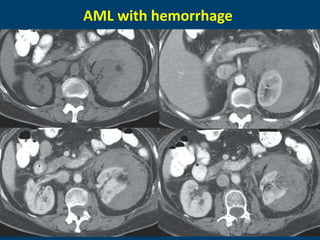

CT:

oInternal hemorrhage may obscure the fat

• Large AML (>4cm in diameter): spontaneous

AML with hemorrhage